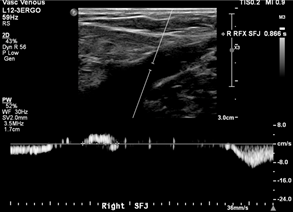

Case: 35F presented with painful right posteromedial thigh and knee vein, concerned for thrombosis given history of DVT in both parents. However, duplex ultrasound was unremarkable with no clots or reflux, and the patient was treated conservatively with compression stockings. She returned 6 years later noting leg fatigue worse at the end of nursing shifts. A repeat duplex performed 6 months earlier showed axial reflux in the right great saphenous and small saphenous veins (Figure 1).

Images showed questionable reflux and it was revealed that the study was performed in a moderate reverse Trendelenburg (RT) position. There was mild reflux at the SFJ in response to Valsalva and a long duration reflux in the thigh and leg in response to distal augmentation with the signal becoming intermittent distally.

Investigation: A low amplitude reflux could cause this pattern with gaps in reflux representing amplitude dipping below the detectable or filtered threshold. However, this could also represent a failure of RT position to generate sufficient downward pressure to achieve complete valve closure, which can result in a valve fluttering effect as blood passes through. We repeated the duplex ultrasound with the patient standing, and this was negative for reflux in any GSV segment.

Discussion: Optimal assessment of venous reflux with duplex imaging requires upright positioning. Tthis serves as a reminder that supine and even RT positioning can cause false positive results in addition to false negatives. Steep RT can provide accurate results and ease the ergonomic burden on technologists, but any questionable results should be double-checked in the standing position.